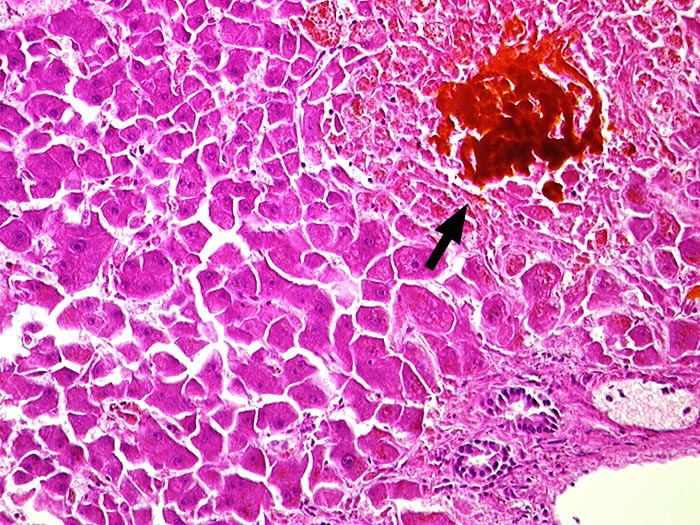

Galleinfarkt bei extrahepatischem Verschlussikterus

Gallig durchtränkte Gruppennekrose. Rechts unten ist ein Portalfeld angeschnitten.

Choledocholithiasis.